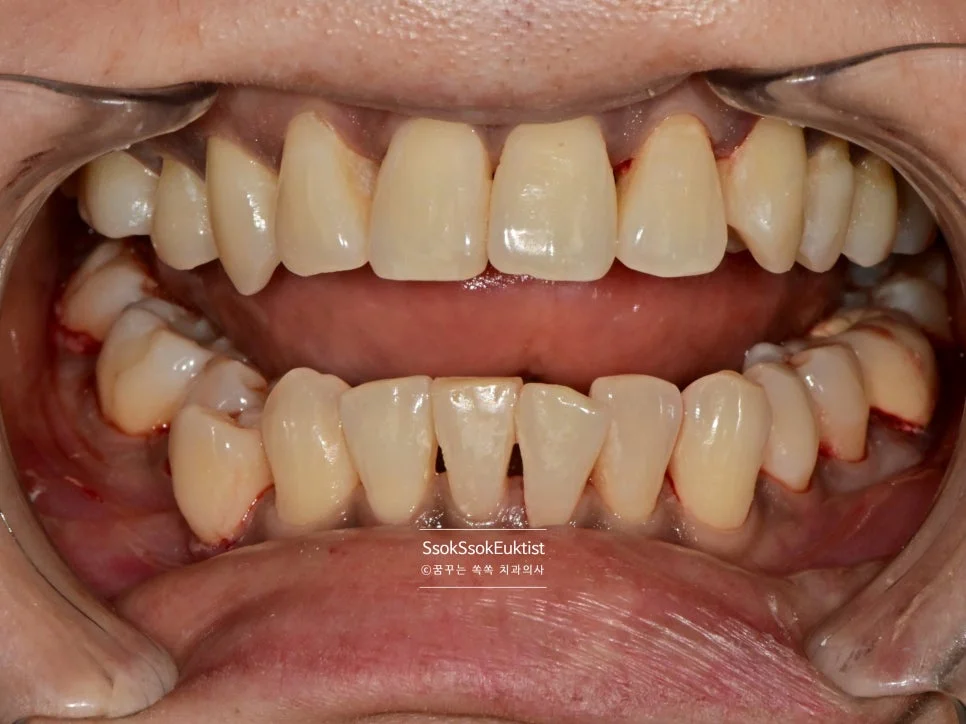

스케일링 전 치석 착색 상태

Before — 스케일링 전

수면 스케일링 후 깨끗한 치아

After — 수면 스케일링 후

왼쪽 위 치경부 우식을 레진으로 예쁘게 치료한 후 스케일링도 시행하였는데요. 비교적 깨끗하고 건강해진 모습이 보입니다~^^